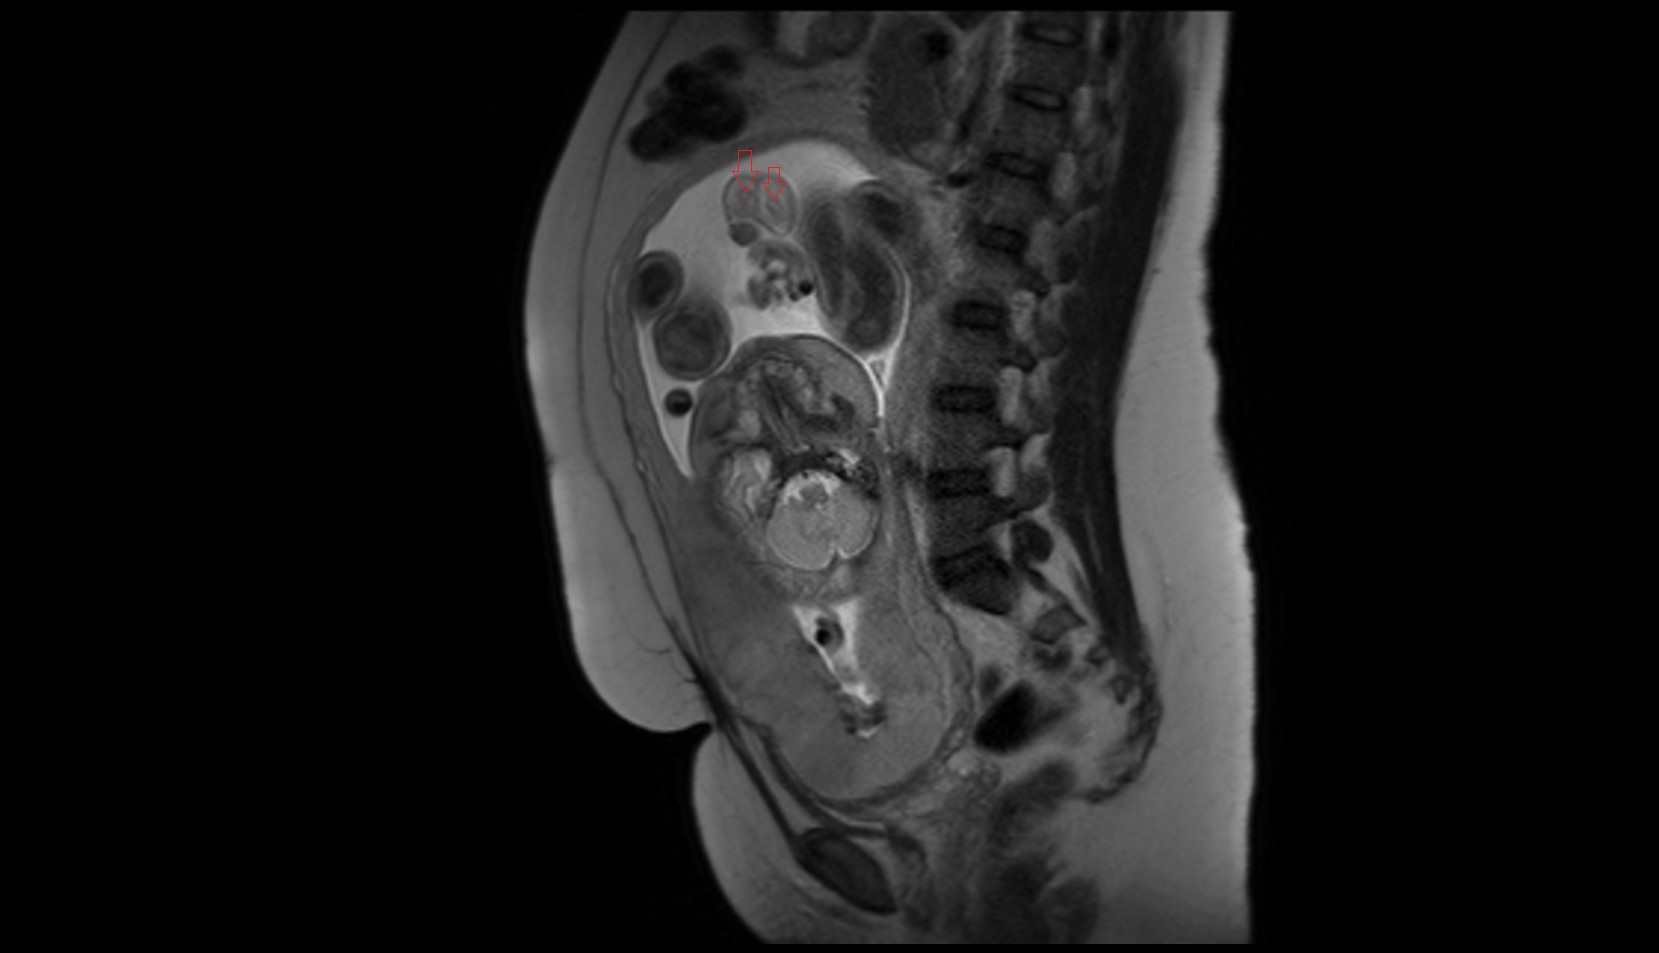

- Placenta

- Uterus (pregnancy)

- Amniotic fluid

- Umbilical cord

- Urinary Bladder in Pregnancy

- Cervix in Pregnancy

- Vagina in Pregnancy

- Fundus of uterus in pregnancy

- Fetal brain